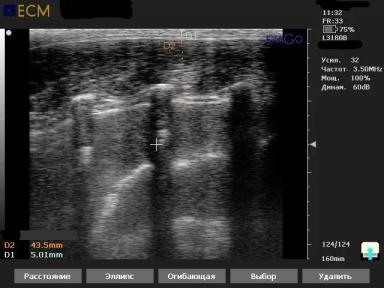

С помощью ультразвука размещая линейный датчик длинной 13 см на последние 4 ребра вдоль позвоночника, можно получить такое изображение, по сути это продольный срез длиннейшей мышцы спины (тот самый карбонад). (первый снимок)

На нём, в основном, определяют 2 показателя, толщина шпика (причем отчетливо видны все 3 слоя (жир более эхогенен чем мышцы, если присмотритесь то посередине отчетливо виден второй слой, отблёскивающей полоской) и глубина мышцы.

Так же можно измерить при помощи УЗИ - площадь мышечного глазка, и с программным обеспечением высчитать % содержания внутримышечного жира (IMF - intamuscular fat).